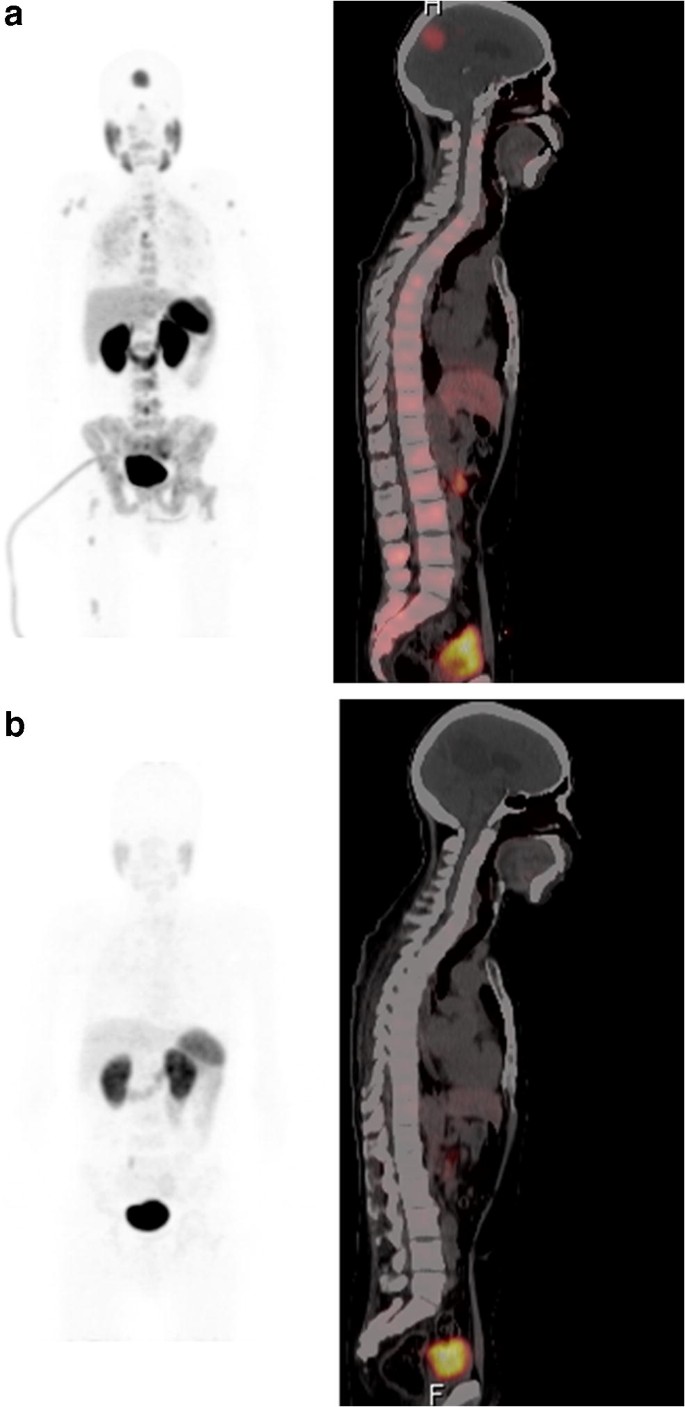

ABSTRACT BACKGROUND AND PURPOSE Brain metastases from prostate cancer are uncommon and their imaging appearance has not been well defined. The main objectives of this study were to evaluate the inc. Treatment of brain metastases from colorectal cancer Current treatment options for brain metastases from CRC include surgical resection whole-brain radiotherapy WBRT stereotactic radiotherapy SRT which includes stereotactic radiosurgery and fractionated stereotactic radiotherapy and chemotherapy alone or in combination.